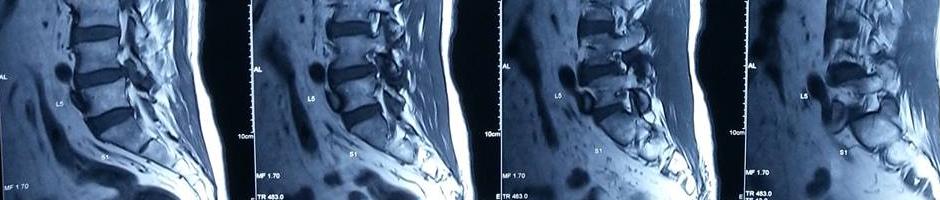

椎間盤突出症 / 軟骨突出症 (Disc Protrusion)

脊骨狹窄症 (Spinal Stenosis)

脊椎滑脫症 (Spondylolisthesis)